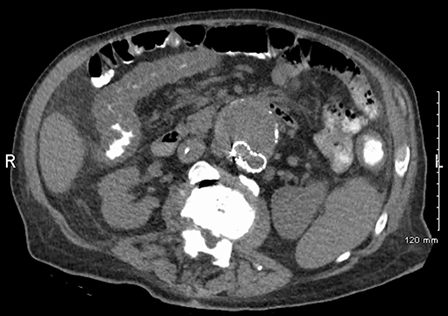

CT scan of the abdomen showing diffuse bowel thickening suggestive of colitis

From the collection of Dr Ali Hassoun